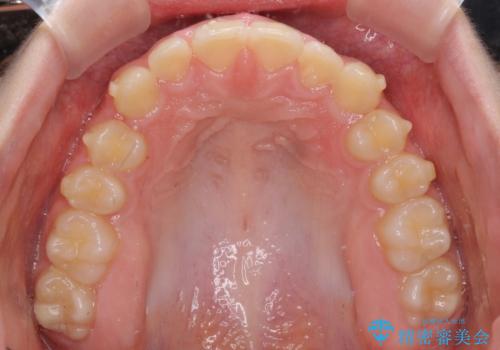

- ヨーロッパにてインビザライン矯正を始めたものの、日本に転居することになり、治療の継続を希望して来院された患者様です。

治療計画に無理がなく、現地担当医と速やかに連絡が取れるとのことで、インビザライン社での転医手続きを行い、継続して治療を行うこととしました。

舌の突出癖により、上下前歯が非接触となっていたため、トレーニングを徹底的に指導し、安定した咬み合わせにより終了させることができました。